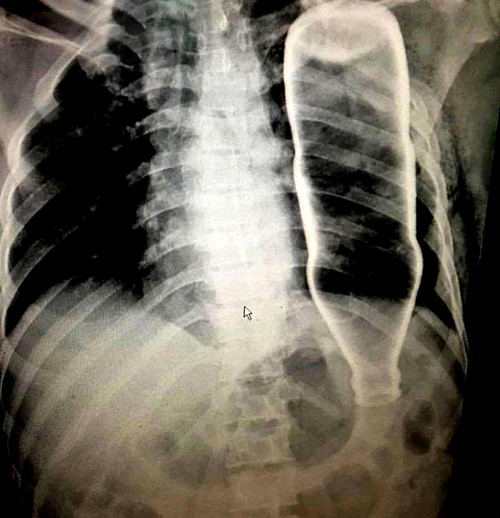

Vỏ chai thủy tinh chui vào ngực

Hồi tháng 5, cú ngã khiến người đàn ông 53 tuổi ở Đà Nẵng gãy hai xương sườn và bị một dị vật xuyên ngực. Mãi khi đến bệnh viện, các bác sĩ mới biết đó là chiếc vỏ chai thủy tinh.

Các bác sĩ đã tiến hành chụp chiếu, kết quả chẩn đoán hình ảnh ghi nhận một vỏ chai làm bằng thủy tinh đang nằm gọn bên trong lồng ngực với tư thế đầu chai chúi xuống dưới. Để xuyên vào cơ thể, chiếc vỏ chai đã làm gãy 2 xương sườn của nạn nhân.